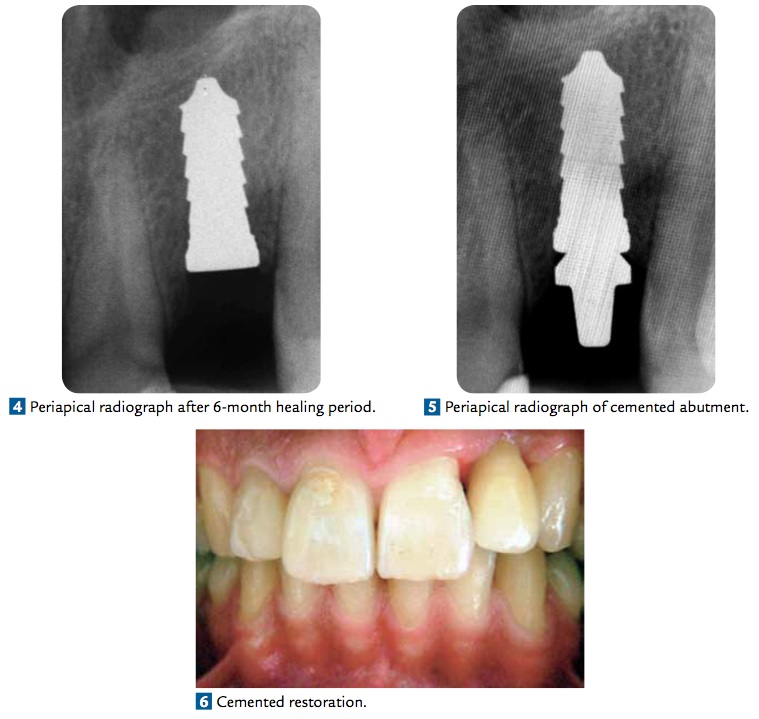

這篇文章是使用Zit-Vario (Germany) zirconia 2 piece implant. 4×11.5mm種在左上側門牙. 過了六個月之後再製作假牙, abutment和crown都是zirconia. 再經過六個月後結果是很好的.